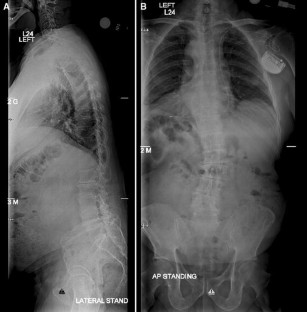

Obtaining a fusion, especially to the sacrum for adult deformity correction remains a challenge. Prior to modern fixation techniques, the reported fusion rates for adult scoliotic deformities were low. However sacropelvic fixation techniques for adult deformity continue to evolve. As a result, modern day pelvic fixation techniques have improved fusion rates at the base of long constructs. The purpose of this article is to discuss the history, indications, and modern fixation techniques for pelvic fixation in the surgical management of adult scoliosis patients.

Sacropelvic fixation should be considered in any patient with a long construct ending in the sacrum, those patients with associated risk factors for loss of distal fixation or high risk for pseudarthrosis at L5–S1, and those undergoing three column osteotomies or vertebral body resections in the low lumbar spine. Current pelvic fixation techniques with iliac screws, multiple screw/rod constructs, and S2-alar-iliac screws are all viable techniques for achieving pelvic fixation.

There is growing evidence that pelvic fixation may become the standard for obtaining long fusions in adult scoliosis. Although technically challenging, in selected cases the use of four pelvic screws and/or four rods across the lumbosacral pelvis can help address pseudarthroses, implant breakage, and screw pullout secondary to osteoporosis. Ultimately, indications and techniques should be individualized to the patient and based on surgeon preference and experience.